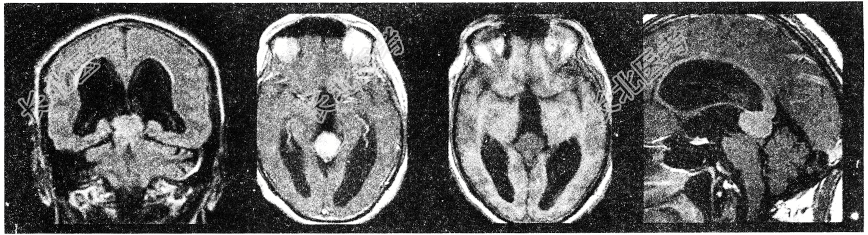

- 单项选择题男孩,15岁。头痛、呕吐, 步态不稳,眼球震颤, 性发育异常,MRI检查如图, 最可能的诊断是

A、生殖细胞瘤

B、畸胎瘤

C、松果体钙化

D、松果体瘤

E、脑膜瘤